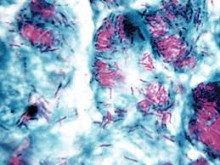

When Gerhard Henrik Armauer Hansen described leprosy In Leprosy: in its Clinical and Pathological Aspects, he examined a section of fresh nodules under the microscope and observed small straight rods in the fluid of the preparation. These were the lepra bacilli that he first discovered in 1871 (Hansen et al., 1895, p. 31). In a fresh preparation, they could be observed to be moving actively. He described them in larger or smaller clumps of a brownish colour that were very granular. They were in the cells and in all the other organs affected with leprosy. He suggested that they may very well serve as a diagnostic indication for leprous affections because, in his experience, they were always present, except in very young nodules.

He remarked that the bacilli must increase very, very slowly and that they probably produced a toxin in very small quantities which “causes no particular injury to the organism, since patients, in spite of numerous nodules with millions or milliards of bacilli, may remain in pretty good health for years.” (Hansen et al., p. 40) He also identified bacilli that broke down into granules as ones that had degenerated. In his numerous attempts to cultivate the bacilli, he had managed only to attain granules. He wrote that “As the bacilli at first multiply in the cells, and the breaking down appears most definitely and freely when the cells are crammed full of bacilli, it is equally possible that it is the result of diminished nutrition, and as they break down more rapidly in the internal organs, it is also possible, indeed probable, that the higher temperature in these organs favours disintegration. As we have unfortunately not been able to cultivate the bacilli, it is at present impossible to form a conclusion. At all events, we regard the transformation into granules as a degeneration, and believe that the bacilli this altered are dead.” (Hansen et al., 1895, pp. 42-3.)

He also remarked that: “As we do not know the manner and method of the primary infection of the organ, we must devote our attention to the search for discoveries like those described above, and to the localisation of the bacilli in general, in order to form an idea of the method of action of the bacilli.” (Hansen et al., 1895, p. 39) *4